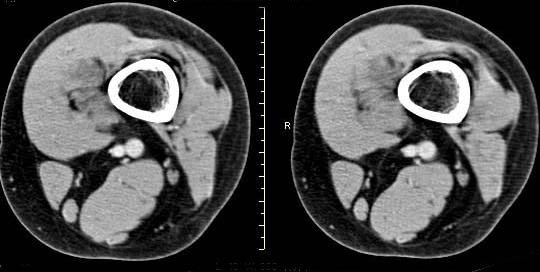

女,24岁,左大腿下部近膝关节处偏内侧有一软组织包块,触之有压痛,平扫示病灶密度不均,形态及轮廓欠规则,无包膜,与周围组织界限不清,增强后显示有明显强化且不均匀强化,本人考虑为该软组织肿块为恶性病变。请大家发表高见!

病灶是有不均匀强化,但病灶与周围组织分界较清,所以性质难定。

病理结果:血管瘤。